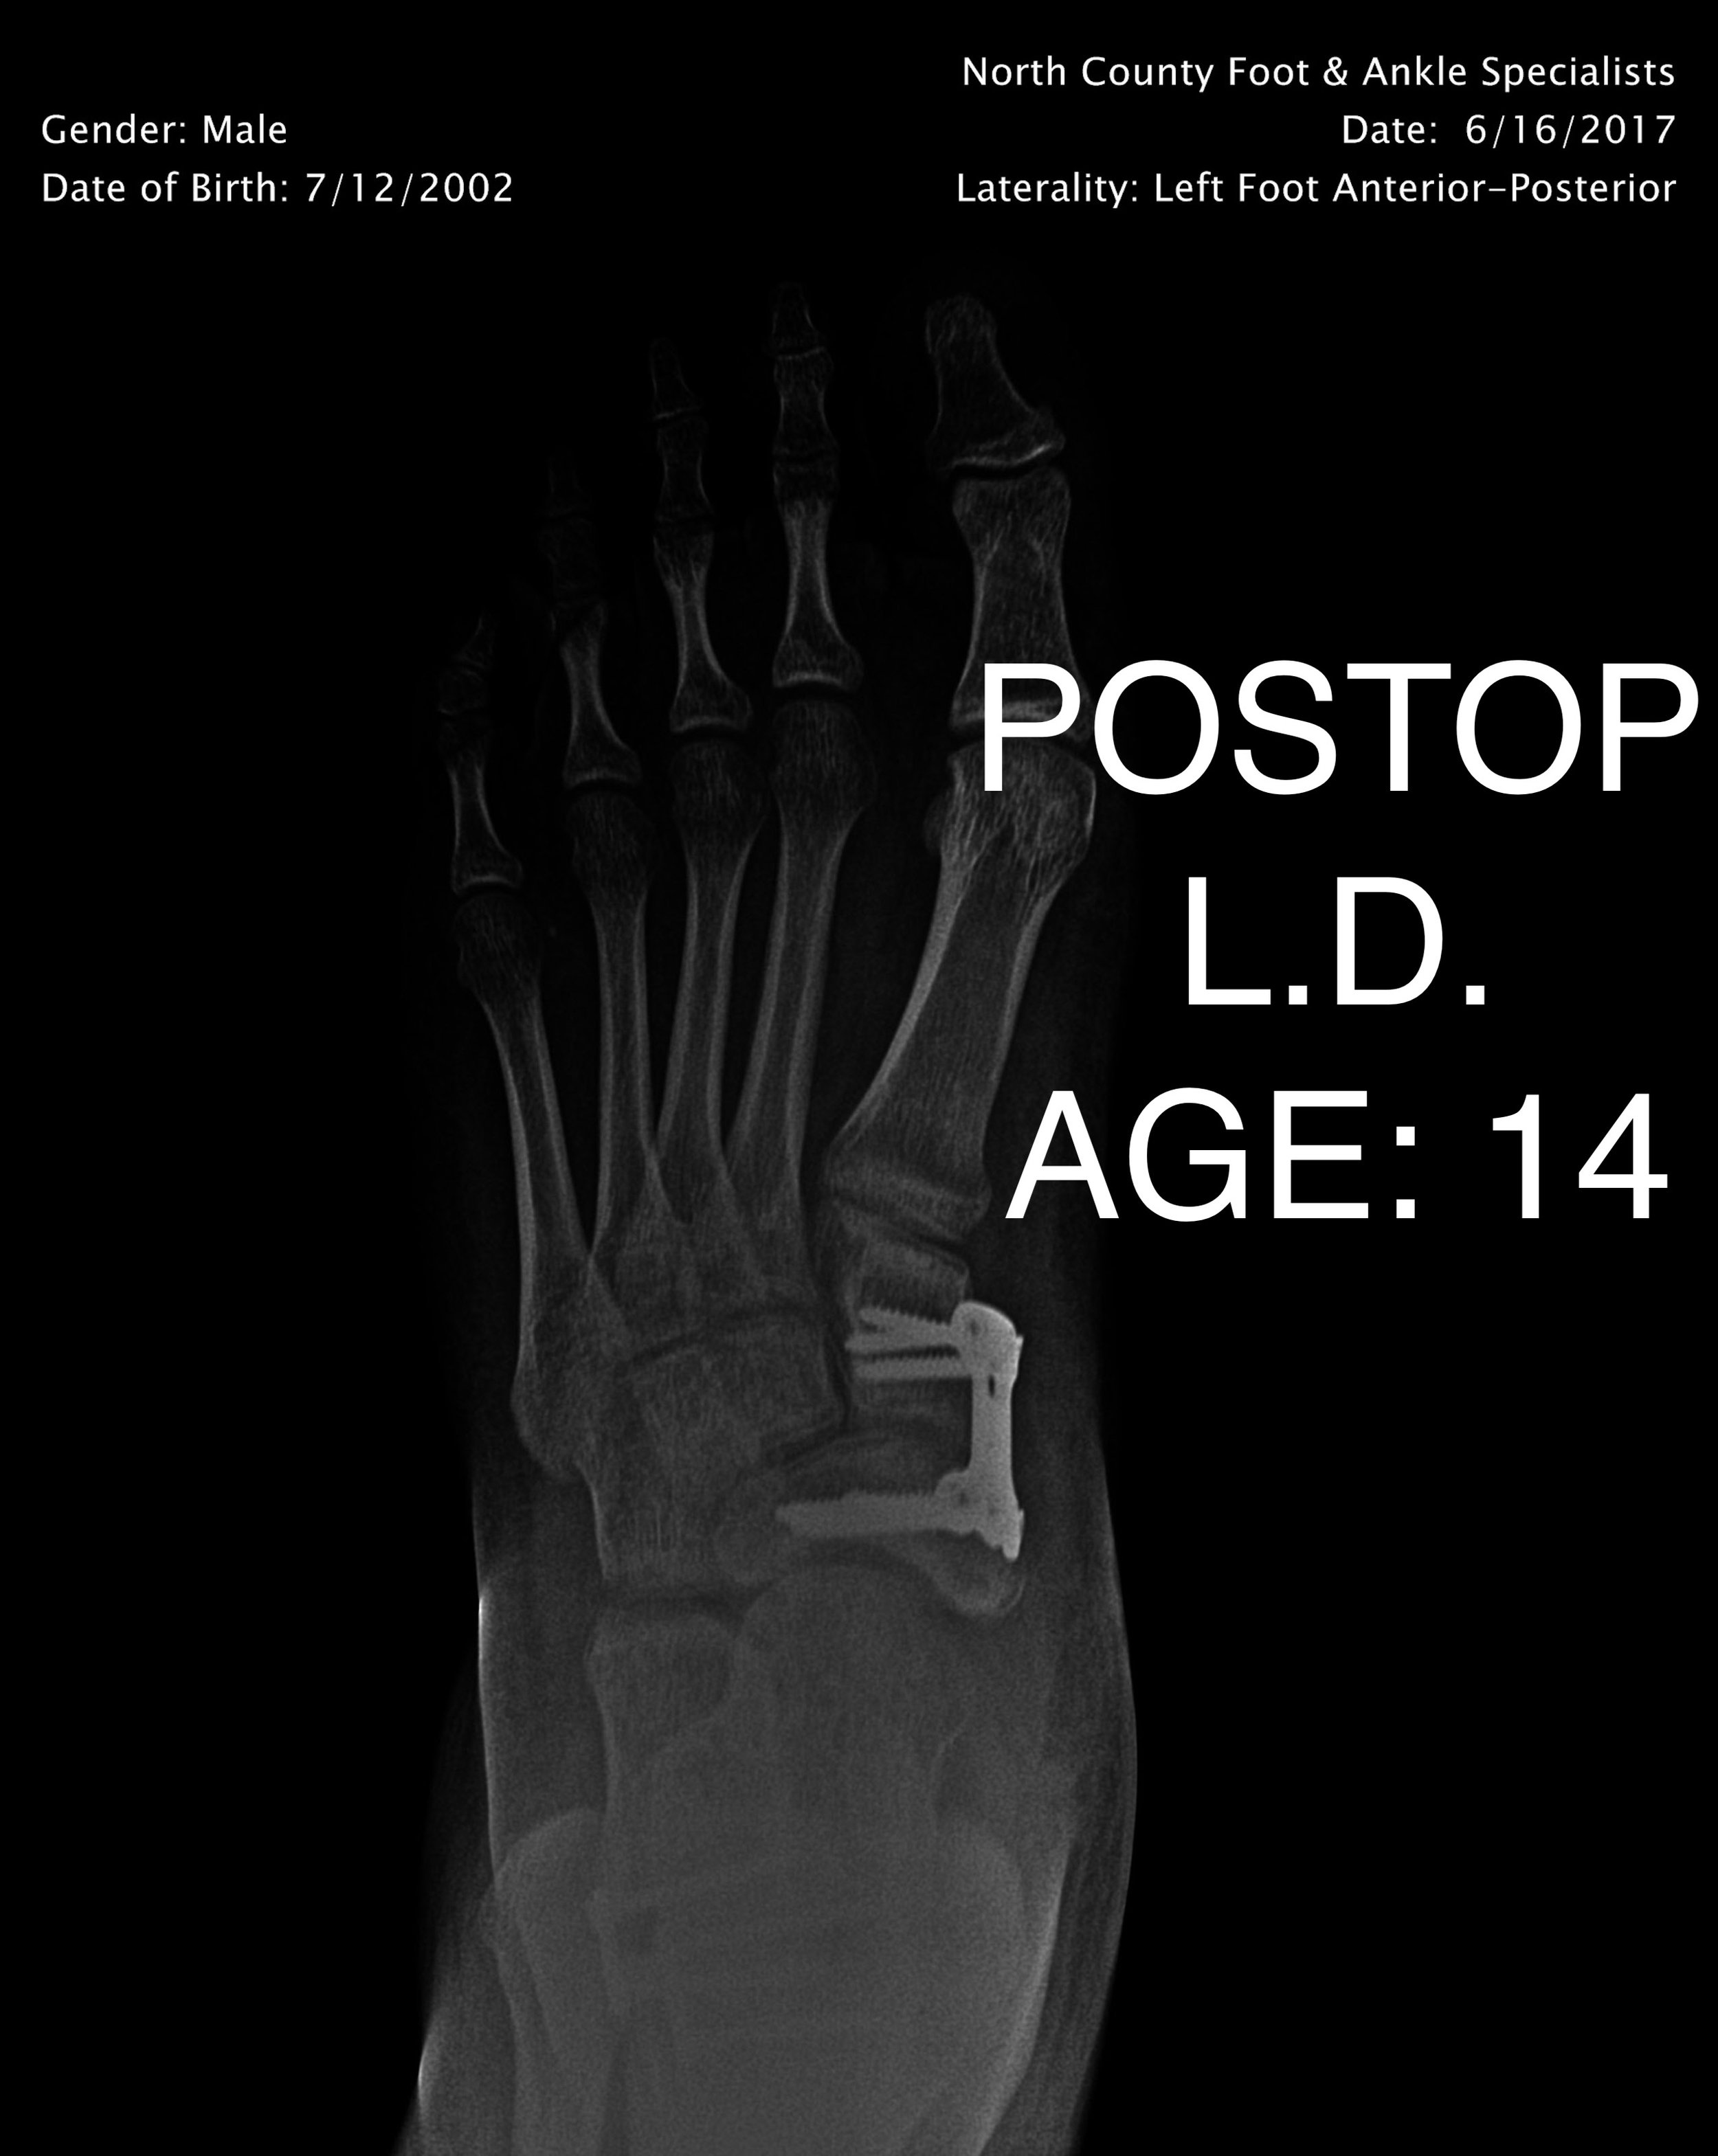

PEDIATRIC FLAT FOOT